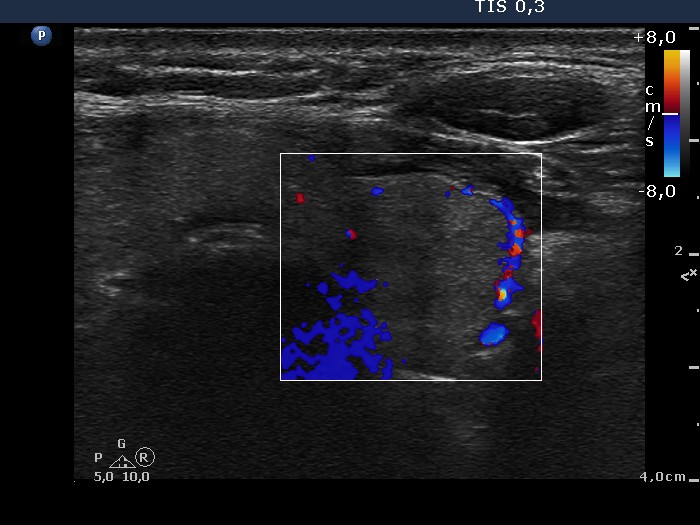

100 consecutive cases of papillary cancer - case 016 (ultrasonographic picture 9)

Left lobe, transverse scan, color Doppler mode. The nodule present perinodular blood flow. The irregular blue patches at the left lower corner of the insert are technical artifacts.